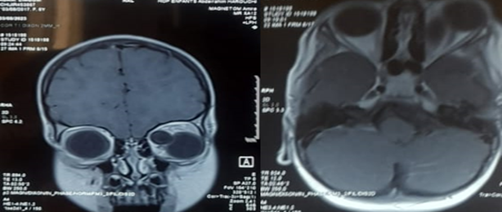

Orbital CT and MRI were performed

CT imaging revealed a well-defined mass, approximately 3 cm in size, enhanced by contrast, causing grade III exophthalmos without globe invasion or evidence of bone erosion. MRI showed a well-demarcated left intraorbital lesion, hypointense on T1-weighted images and hyperintense on T2-weighted images, suggestive of a benign hydatid cyst. The patient underwent surgical excision of the lesion. Histopathological analysis confirmed the diagnosis of a hydatid cyst. Postoperative clinical evolution of the left eye was marked by a gradual resolution of inflammatory signs and regression of the exophthalmos.

Figure 3: Axial and frontal section of T1 MRI showing the orbital cyst